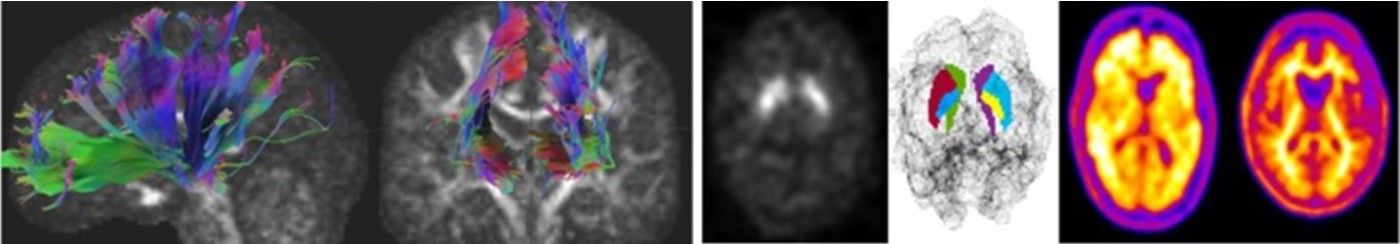

2. Development of imaging biomarkers for neurodegenerative diseases

The development of biomarkers for Alzheimer's disease and Parkinson's disease is an essential issue in a society that aims for long and healthy life. We aim to develop new imaging biomarkers from molecular images such as MRI, PET, and SPECT, in addition to conventional quantitative values. We search for effective image biomarkers for early diagnosis, stratification, and prognosis and develop classification and prognosis models using machine learning.

In addition, we are also working on dose assessment using Monte Carlo simulation in nuclear medicine. (Takuro Shiiba)

3. Development of analyzing method for brain function and structure using MRI and image processing techniques to improve the accuracy for assessment

Magnetic resonance imaging (MRI) allows to show the contrast depending on the condition and behavior of water molecule in tissues, and gives very detailed images of soft tissues like the brain. Our research focuses on developing analysis methods to noninvasively assess of brain function and structure in neurological disorders using MRI, and image processing techniques to improve the accuracy to assess.(Kazuki Takano)